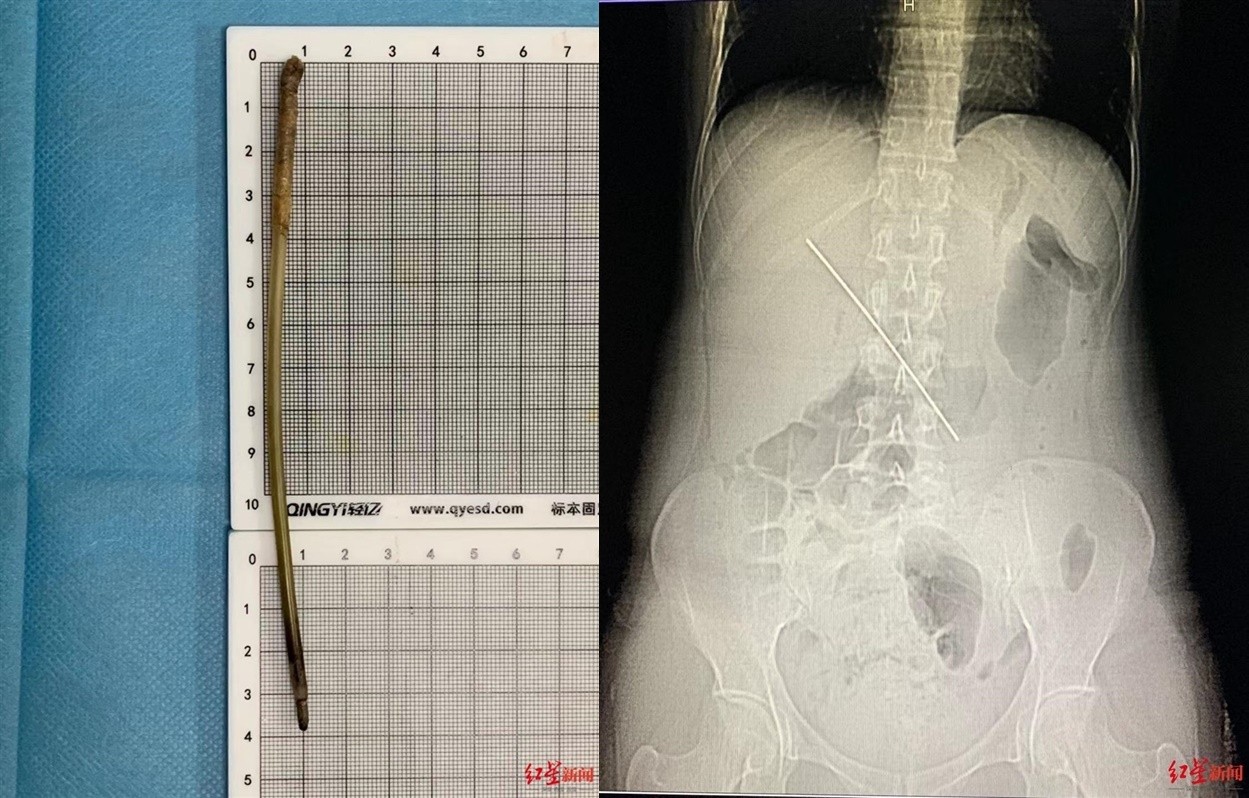

▲女子喝水竟然喝下長釘。(圖/翻攝自《紅星新聞》)

四川成都一名38歲女子近來因為劇烈腹痛就醫,沒想到體內藏了一根15公分長鐵釘,幾乎到達肝臟的大血管門靜脈處,一不小心就有可能造成嚴重出血甚至喪命,而她之所以會吞下長釘竟然是因為喝下一瓶礦泉水。

《紅星新聞》報導,38歲米姓女子22日晚間11時到四川大學華西醫院急診科就診,醫生表示,患者因為嚴重腹痛前來,雖然意識清楚,但已經痛到躺在床上完全不能動,斷層掃描發現體內有一根15公分長金屬物質。

醫生表示,由於異物在患者體內時間較長,已造成多個部位出血,一端更達到肝臟的大血管門靜脈,若是沒有小心處理恐怕會造成嚴重出血,最後選擇對患者傷害性較少的內視鏡方式,20分鐘順利取出異物,患者的劇烈腹痛感也立即獲得緩解。